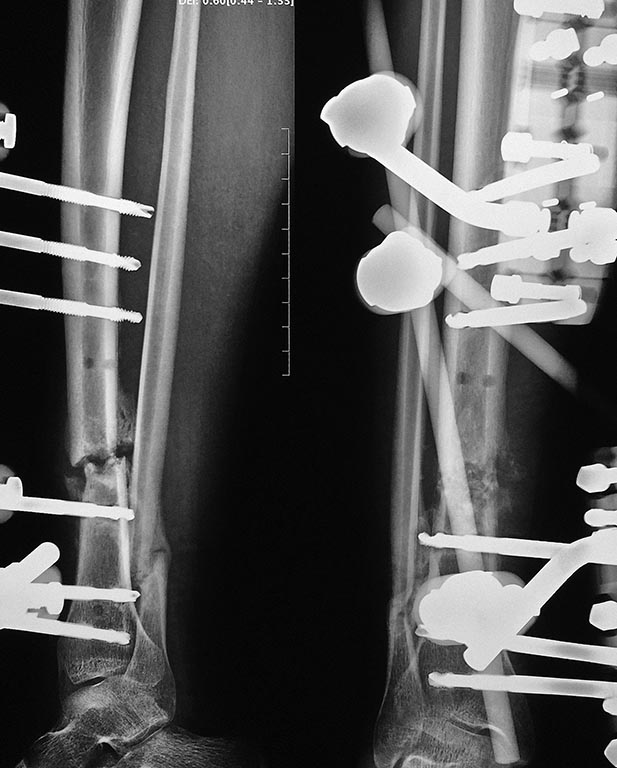

Больной 18 лет, 5 месяцев назад сбит автомашиной, проходил лечение в нашем отделении с диагнозом

"Автотравма, ЗЧМТ среднетяжелая, ушиб головного мозга, открытый перелом нижней челюсти, закрытый перелом правой бедренной кости, открытый перелом костей правой голени". 5 месяцев назад выполнены открытые репозиции отломков бедренной кости и нижней челюсти, остеосинтез. На голени была ранка в проекции перелома 5х5 мм., наложен стержневой аппарат. Ранка зажила через 2 недели после травмы без признаков воспаления. Переломы бедренной кости и челюсти консолидировались, но контрольных рентгенограммах костей голени нет сращения большеберцовой кости. Местно - признаков воспаления нет. Ходит на костылях, приступая на больную ногу. Посоветуйте, пожалуйста, тактику дальнейшего лечения. Заранее благодарны за любые предложения!